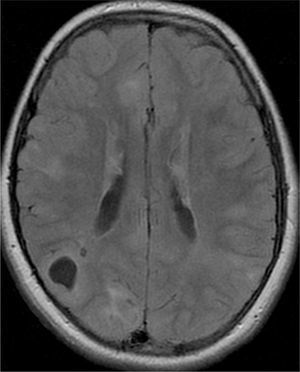

La epilepsia aparece generalmente en el primer año de vida y una forma de presentación frecuente son los espasmos epilépticos (36-96%)10. El número y, en particular, el volumen total ocupado por hamartomas glioneuronales están relacionados con la presencia de disfunción cerebral grave (epilepsia refractaria y/o deterioro cognitivo moderado a grave)1,11. También se ha demostrado la asociación entre el grado de gravedad de la epilepsia y la presencia de tuberomas corticales con aspecto quístico12.

Las resonancias magnéticas (RM) cerebrales evaluadas han sido revisadas de forma independiente por el mismo examinador de la especialidad de Neurorradiología y se estudiaron las siguientes variables: número de tuberomas, localización supra o infratentorial, el número de lóbulos cerebrales con lesiones, el número y la lateralización de tuberomas con quistes, las líneas de migración radial de la sustancia blanca, los nódulos subependimarios y los astrocitomas de células gigantes. Los pacientes efectuaron los estudios de RM en equipos GE Signa 1.5T y en RM Philips Achieva 3.0T TX (3 pacientes), en el Departamento de Neurorradiología del CHP. Después de obtenida la imagen localizadora en el plano sagital, para identificar las comisuras anterior y posterior, se han adquirido imágenes en paralelo al plano intercomisural: FLAIR, T2 SE, T2 *, T1 SE y T1 SE tras contraste.

Se definió tuberoma como una lesión hiperintensa corticosubcortical en FLAIR y líneas de migración radiales como hiperintensidades lineales en FLAIR, que se extiende desde la superficie ventricular hasta el tuberoma cortical. Los nódulos subependimarios han sido investigados en cualquier ventrículo, con origen en la pared ventricular y con proyección hacia el interior de los mismos.

Se consideraron tuberomas con quistes subcorticales las lesiones con una señal similar al del líquido cefalorraquídeo en todas las ponderaciones y con un anillo hiperintenso alrededor en T2. Los tuberomas o nódulos subependimarios calcificados han presentado una hiposeñal en T2 y T2*. Una vez que la cantidad o el número de tuberomas en el parénquima encefálico son indicados como el mejor marcador de gravedad de epilepsia y de la función cognitiva1, se efectuó una evaluación cualitativa por medio la frecuencia de tuberomas. En cada lóbulo cerebral, la densidad de tuberomas se relaciona con la carga de lesión cerebral obtenida por la evaluación del número total de tuberomas y de la afectación de cada lóbulo por los tuberomas. Se consideró como elevada carga de lesión la afectación de todos los lóbulos por tuberomas, en pacientes con número total de tuberomas más de 15. No han sido evaluados la densidad o el volumen de tuberomas por técnica cuantitativa de segmentación automática de tuberomas por inaccesibilidad a software apropiado.

El 74,3% (26) de las RM disponibles han sido revisadas en todos los lóbulos cerebrales en el 76,9% (20) de los pacientes, en los cuales se identificaron más de 15 tuberomas, es decir, una elevada carga de lesión. En el 96,2% (25) de los enfermos se observaron líneas de migración radial (fig. 1). Estaban presentes nódulos subependimarios en el 84,6% (22), la mayoría de los cuales con calcificación y, en 3 casos, con captación de contraste (fig. 2). En el 23,1% (6) de los enfermos se encontraron tuberomas infratentoriales. Siete casos presentaban tuberomas con aspecto quístico (26,9%), 6 de los cuales en localización yuxtacortical y uno infratentorial (fig. 3). Es de referir un caso con probable astrocitoma de células gigantes, bajo control dimensional, en la región del agujero de Monro, sin signos de hidrocefalia (fig. 4). Ninguno de los enfermos presentaba atrofia focal.

De los enfermos con mutación en TCS2 identificada, solamente en uno la RM no ha sido revisada, presentando todos los restantes una elevada carga de lesión. Uno de 5 pacientes con mutación TSC1 presentó elevada carga de lesión. De los 5 casos asociados a epilepsia refractaria, 2 presentaron tuberomas con alteraciones quísticas.